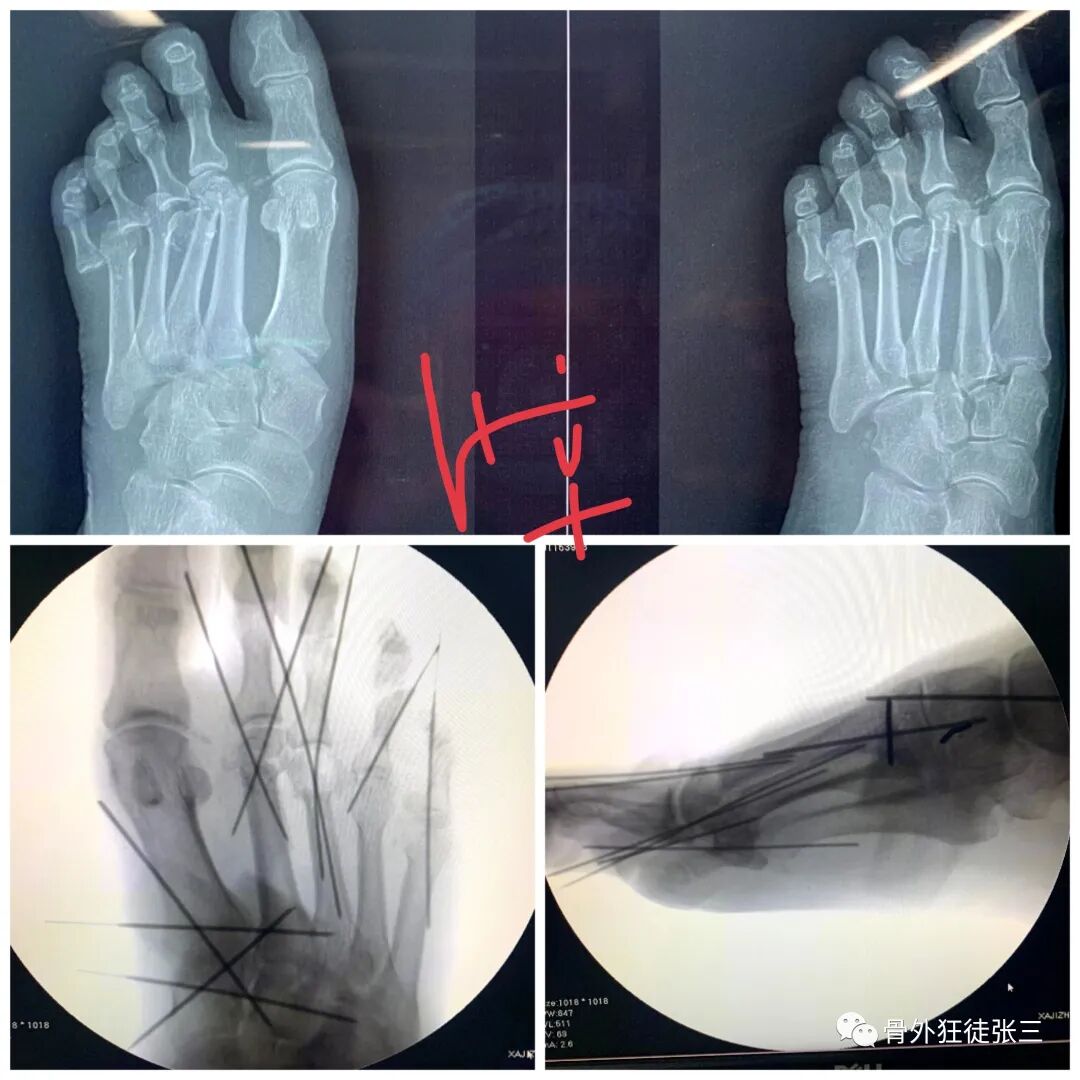

病例8,第234跖骨骨折,闭合穿针

病例33,开放性Lisfranc损伤+第2345跖骨骨折脱位